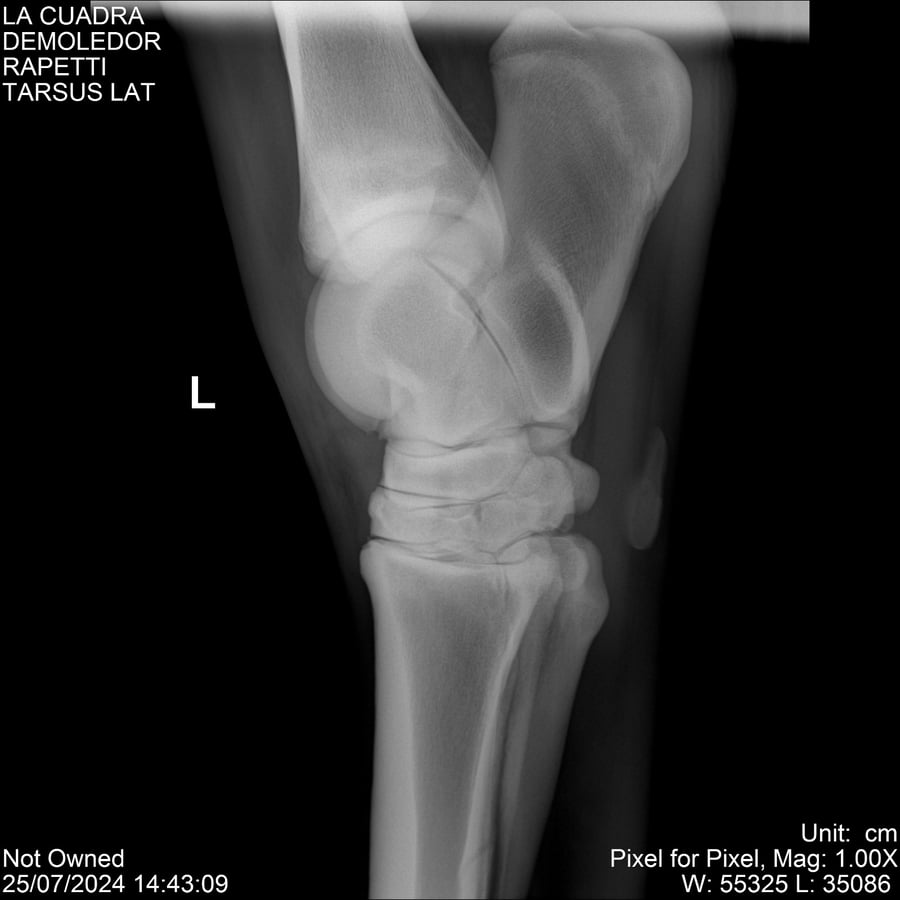

LOTE 14, DEMOLEDOR 🔥 🔥 🔥 Lote Anterior Volver al remate Lote Siguiente Ficha Contacto Montevideo - Ficha del Lote Identificador: #284454 Categoría: Yeguarizos Montevideo - 89 Visualizaciones ClicData Contacto Empresa: Abelenda N. R., Walter Hugo Nombre*: Teléfono* : E-mail* : Mensaje Enviar Registrese gratis Este contenido Exclusivo está disponible sólo para usuarios registrados Ingresar